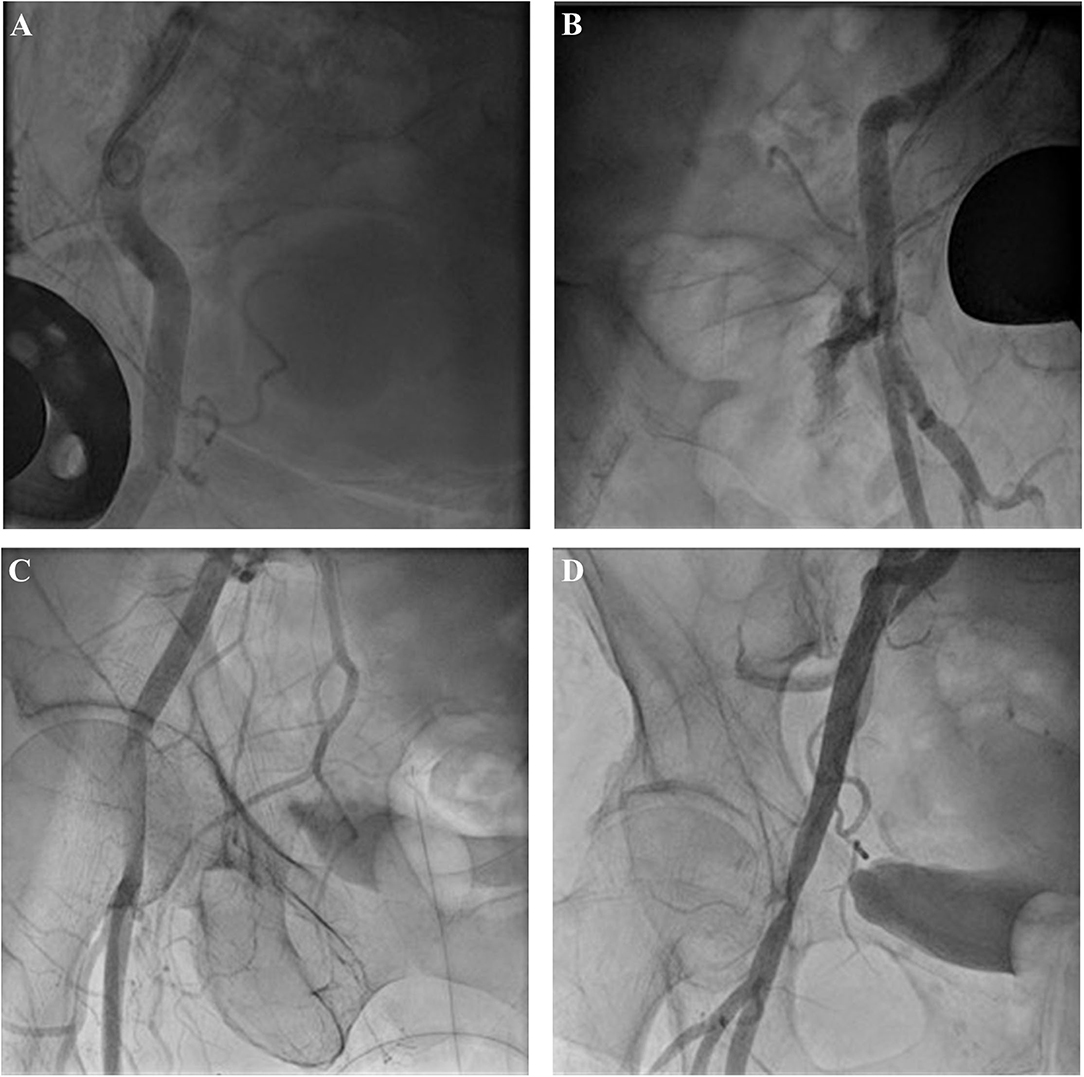

The last angiogram of the access site was evaluated retrospectively concerning any sign of leaks, dissection/endovascular flap, stenosis (lumen reduction of ≥50%), and total occlusion of the CFA (Figure 2).

Evaluation of angiogram after use of closure device: minor leak (A), severe leak (B), dissection (C), and stenosis with minor leaks (D).

The most frequently implanted size of BLE was 25 mm (43%), followed by 27 mm (38%), and 23 mm (19% of BLE). For the MEV, the most frequently implanted size was 29 mm (35.5%) followed by 26 mm (29%), 34 mm (28%), and 23 mm (7.5%). The procedural data with respect to VC are shown in Table 3. Patients receiving MEV had minor VC more often (64 vs. 36% p = 0.003), whereas major VC differed only numerically without statistical significance (2 vs.0.5%, p = 0.18). In relation to the difference in valve type distribution concerning VC outer sheath/delivery, the catheter diameter was smaller in patients with VC. SFAR however was not associated with VC in the study cohort (p = 0.74 for SFAR derived from mean CFA diameter; p = 0.18 for SFAR derived from minimal CFA diameter.) The results of the final angiography of the access site after use of the closure device (and before possible intervention are displayed in Figure 4. A leak of any sort was quite frequent with the 41.5%, however, the results of the angiography were not predictive for VC.